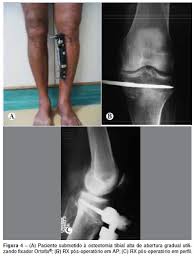

Dr Marcelo Tostes Osteotomia Da Tibia